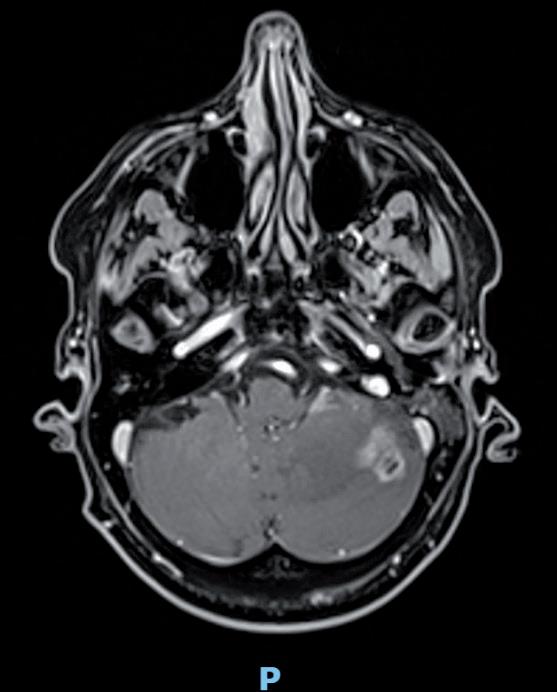

Tuttavia, nonostante la buona risposta iniziale, la TC total body con mezzo di contrasto del 28/12/2023 (figura 1) evidenzia progressione epatica ed encefalica con un quadro radiologico che mostra sovvertimento encefalico diffuso caratterizzato da numerose lesioni secondarie (almeno 10) a netta impregnazione contrastografica a sede sia cerebrale che cerebellare, prevalentemente subcentimetriche, la maggiore di 13 mm in nucleo-capsulare sx con nucleo necrotico e modesto alone edemigeno perilesionale.

La paziente, asintomatica sul piano neurologico e con marcatori tumorali negativi, viene sottoposta previo consulto multidisciplinare, a radioterapia panencefalica con risparmio dell’ippocampo con tecnica IMRT (30 Gy in 10 frazioni) e candidata poi a trattamento di II linea con T-DXd (5,4 mg/kg) q21, supportati dai dati di efficacia riportati dal DESTINY-Breast03, dalle analisi di sottogruppo degli studi DESTINY-Breast01, -02, -03 e dagli incoraggianti risultati preliminari degli studi DEBBRAH e TUXEDO-1.

La rivalutazione strumentale effettuata dopo 4 cicli di trattamento (figura 2) ha mostrato risposta intracranica completa ed epatica parziale. Lo studio della regione mammaria e ascellare con ecografia mammaria e mammografia ha mostrato assenza di lesioni infiltrative con presenza in sede retroareolare sx di un cluster di microcalcificazioni in assenza di linfoadenopatie ascellari. Lo studio tomografico con finestra per osso ha confermato la sovrapponibilità delle lesioni ossee rispetto alla precedente TC, in assenza di fratture patologiche. La paziente tuttora non ha mai manifestato eventi scheletrici secondari né riferisce dolore.